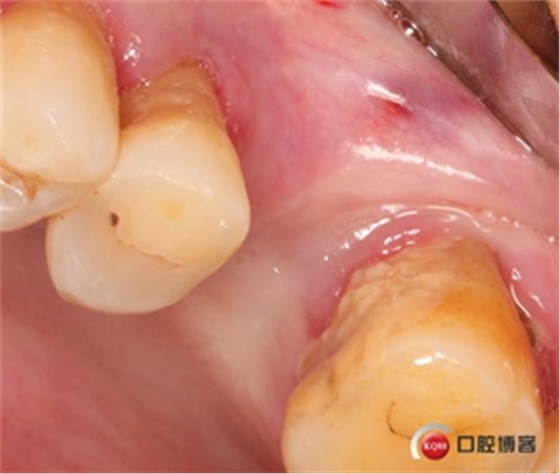

患者女性,58歲,身體健康,無不良咀嚼習(xí)慣,不吸煙、不飲酒。兩年前因左上后牙反復(fù)咬合痛,嚴重影響進食就診,檢查發(fā)現(xiàn)26號牙根尖周炎癥明顯,周圍骨吸收嚴重。拔除患牙,徹底掻刮,由于骨缺損嚴重,沒能即刻種植。6個月后來門診種植。

骨高度僅有3mm,寬度充足。計劃外提升,根據(jù)骨質(zhì)情況決定是否同期植入植體,切開翻瓣,暴露上頜竇頰側(cè)骨壁。